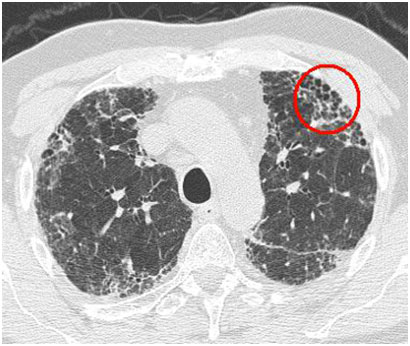

圖片來源網(wǎng)絡(luò)

目前高分辨率CT(HRCT)檢查是確診特發(fā)性肺纖維化的必要手段。對于特發(fā)性肺纖維化患者而言,早診斷、早治療至關(guān)重要,如果患者在疾病初期就能得到及時有效的診治,便能有效延緩疾病進(jìn)展,改善生活質(zhì)量。